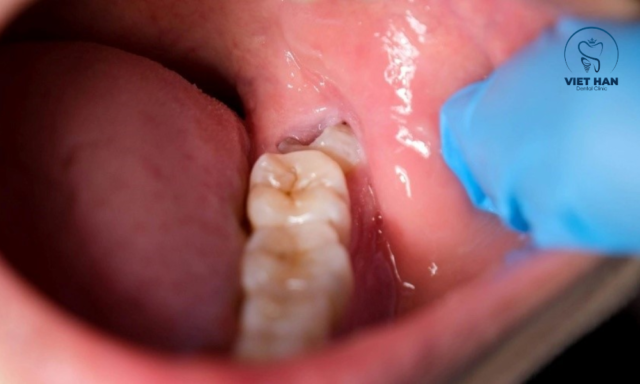

Phương pháp truyền thống là kỹ thuật được áp dụng từ lâu trong nha khoa. Bác sĩ sẽ sử dụng các dụng cụ như dao rạch, kìm và bẩy để tách nướu, mở ổ xương và lấy răng ra ngoài. Phương pháp nhổ răng khôn truyền thống có ưu điểm là chi phí thấp, phù hợp với nhiều đối tượng và được áp dụng rộng rãi tại hầu hết các phòng khám nha khoa. Kỹ thuật này đặc biệt hiệu quả trong những trường hợp răng khôn mọc thẳng, dễ xử lý.

Nhổ răng khôn bằng kìm và bẩy là phương pháp truyền thống.

Tuy nhiên, thời gian thường lâu hơn, người bệnh cần há miệng lâu nên dễ mỏi hàm. Sau tiểu phẫu có thể xuất hiện tình trạng sưng đau hoặc chảy máu kéo dài, đồng thời vẫn tiềm ẩn nguy cơ sang chấn mô mềm và xương hàm nếu thao tác phức tạp. Dù vậy, đây vẫn là phương pháp phổ biến với nhổ răng đơn giản hoặc muốn tối ưu chi phí.